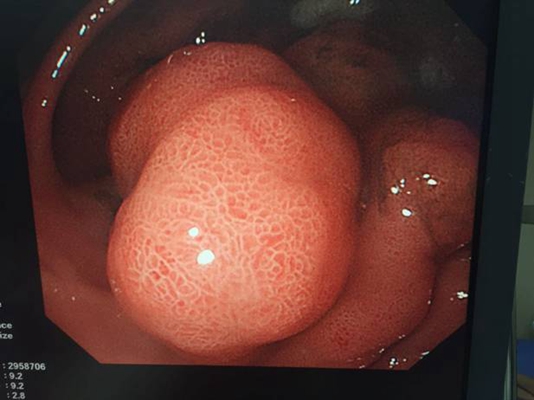

食道炎圖片